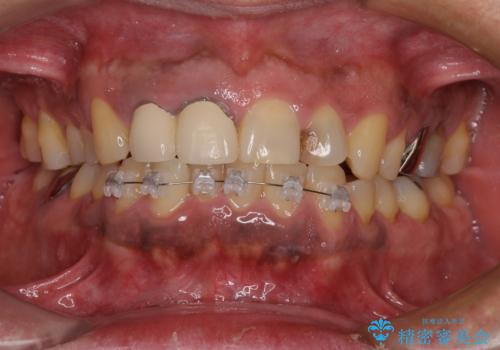

骨格性のディープバイト 補助装置を併用したワイヤー矯正治療で咬み合わせを改善